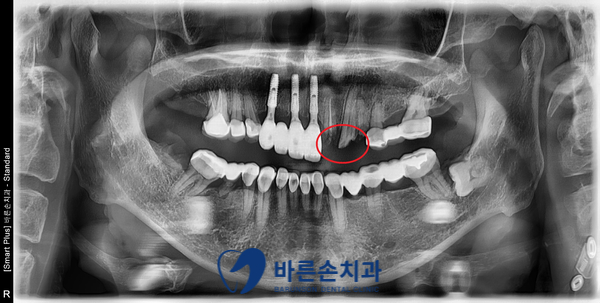

초진 사진 입니다.

예전에 씌워 놓았던 보철물 내부에서 충치가 생겨, 한거번에 부러졌습니다.

남은 치아 부분이 거의 없고, 그 마저도 많이 썩어있는 상태입니다.

이런 경우, 아쉽지만 치아 3개 모두를 발치해야 합니다ㅜㅜ